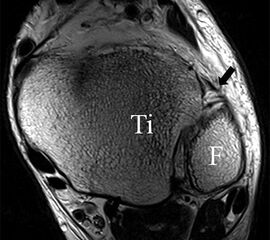

Die Kombination aus 3 Tesla Hochfeldtechnik und/oder Verwendung hochauflösender Spulen (Empfangseinheiten des Signals) erhöht die Signalausbeute. Dies erlaubt mit akzeptablen Messzeiten (3-4 Minuten pro Sequenz) im Routinebetrieb eine Darstellung mit einer Schichtdicke von 1-2 mm und einer Ortsauflösung von 0,2 x 0,2 mm in der Schichtebene in den anatomisch am besten zeichnenden 2D Turbospinechosequenzen. Der Unterschied der diagnostischen Wertigkeit zwischen einer kernspintomographischen „Standarduntersuchung“ und einer HR-MRT wird besonders in der chondralen Diagnostik sichtbar (Abb. 1 a-c). Unter Verwendung von 3D Sequenzen, die jedoch entscheidende Schwächen bei der Darstellung der Ligamente aufweisen, werden sogar Schichtdicken weit im Submillimeterbreich erreicht. Eine weitere Erörterung der Sequenz spezifischen Eigenheiten soll jedoch an dieser Stelle unterbleiben.

Das Ligamentum fibulotalare anterius entspricht einer bifaszikulären Struktur (Abb. 2 a) mit interponierendem fibrovaskulärem Gewebe (S. K. Sarrafian (ed). 2003). Es gibt jedoch Variationen der Ligamentanatomie. In 55% liegt das LFTA als bifaszikuläres Band (Abb. 2 a), in 9% als monofaszikuläre Bandstruktur (Abb. 2 b) und in 36% als multifaszikuläre, striäre Variante (Abb. 2 c) vor 3.

PD fs HR axial. Klare Darstellung eines filigranen, knapp über 1 mm breiten LFTA (Pfeil). Fibula (F).

Abbildung 3

Das LFTA verbindet die antero-inferiore Fibulaspitze mit dem Processus lateralis tali und inseriert hier an einem oder zwei kleinen Tuberkeln 3. Der in Neutralposition horizontale Verlauf erleichtert die kernspintomographische Darstellung in dieser Standardebene. Das LFTA weist durchschnittlich eine Breite von knapp über 2 mm auf 4. Somit sind bei einer Routinedarstellung in 3 mm Schichtdicke Anschnittsphänomene, die die Diagnostik erschweren, regelmäßig anzutreffen. Dementsprechend sind auch die ligamentären Subfaszikel nicht zu differenzieren. In koronarer Darstellung ist dies aufgrund der hohen Auflösung in der Schichtebene jedoch möglich (Abb. 2 a-c), wobei hier wiederum eine Integritätsbeurteilung des Bandes erschwert ist. Unter Verwendung hochauflösender Techniken im Millimeterbereich (Schichtdicke) sind hingegen auch in der axialen Ebene die subfaszikulären Strukturen zu beurteilen (Abb. 3).